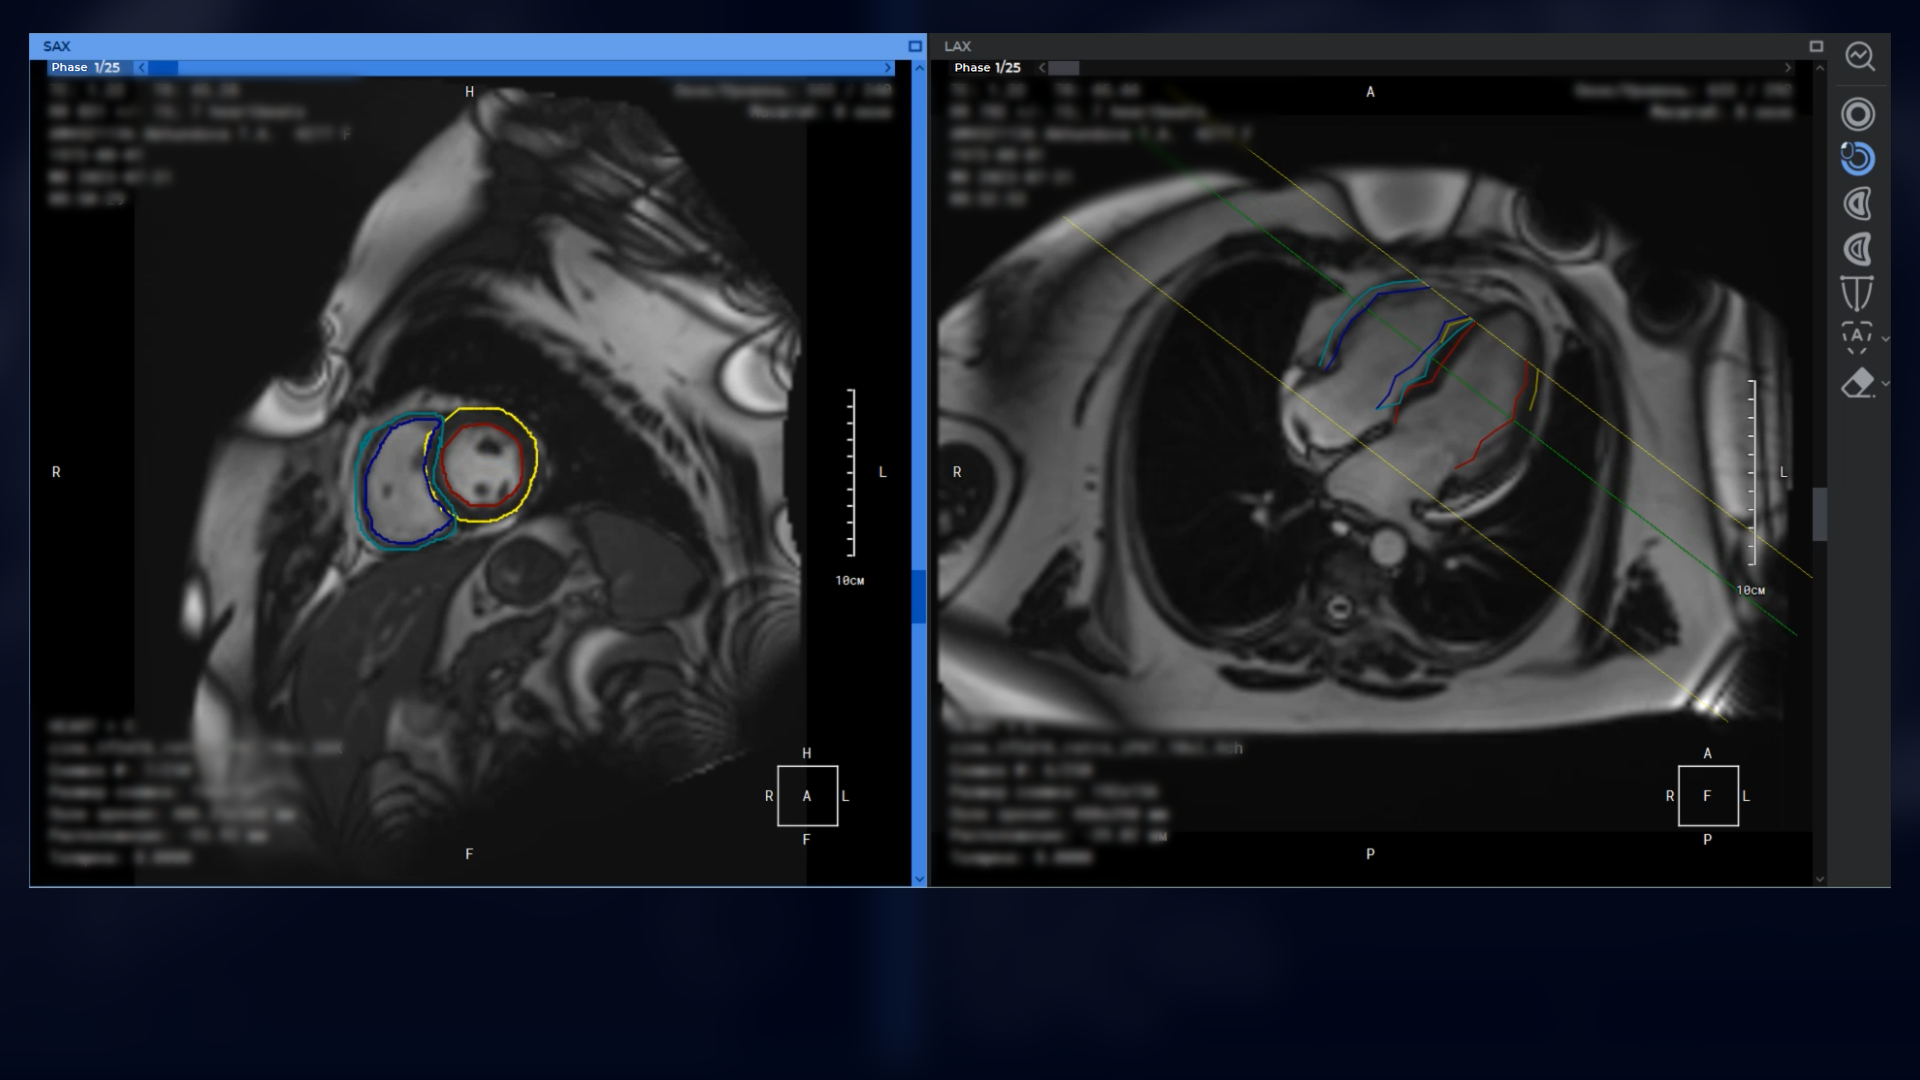

Advanced capabilities for working with 3D reconstructions

Advanced multiplanar reconstruction capabilities